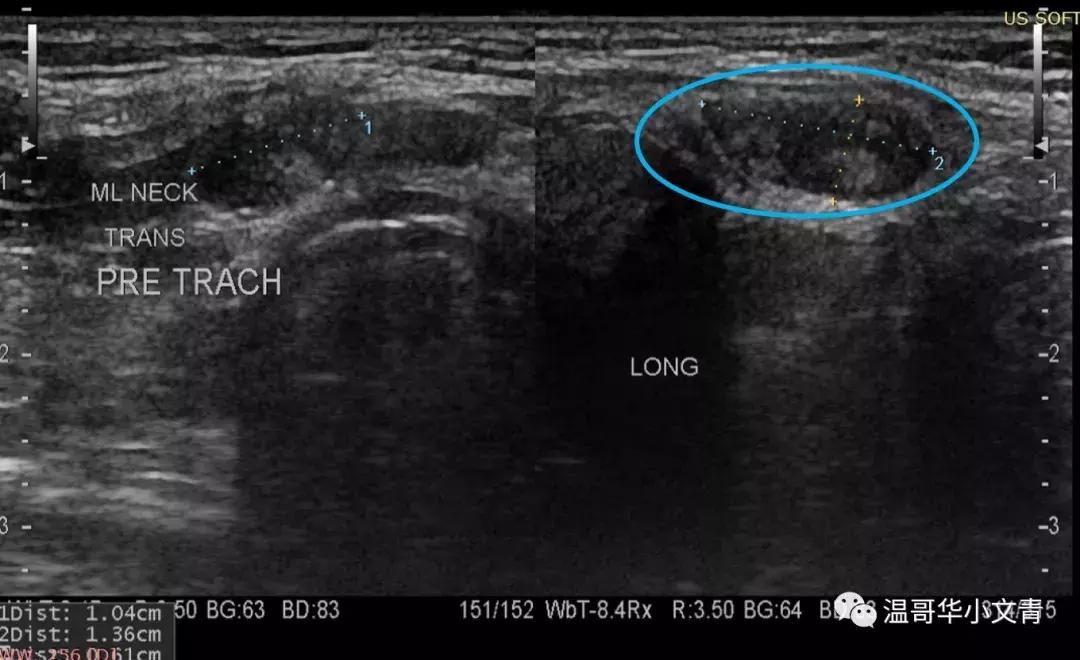

以上图为例

蓝色所指是气管前淋巴结

这个淋巴结明显内部回声不均匀,非常可疑

出现淋巴结转移的微小癌不适合观察